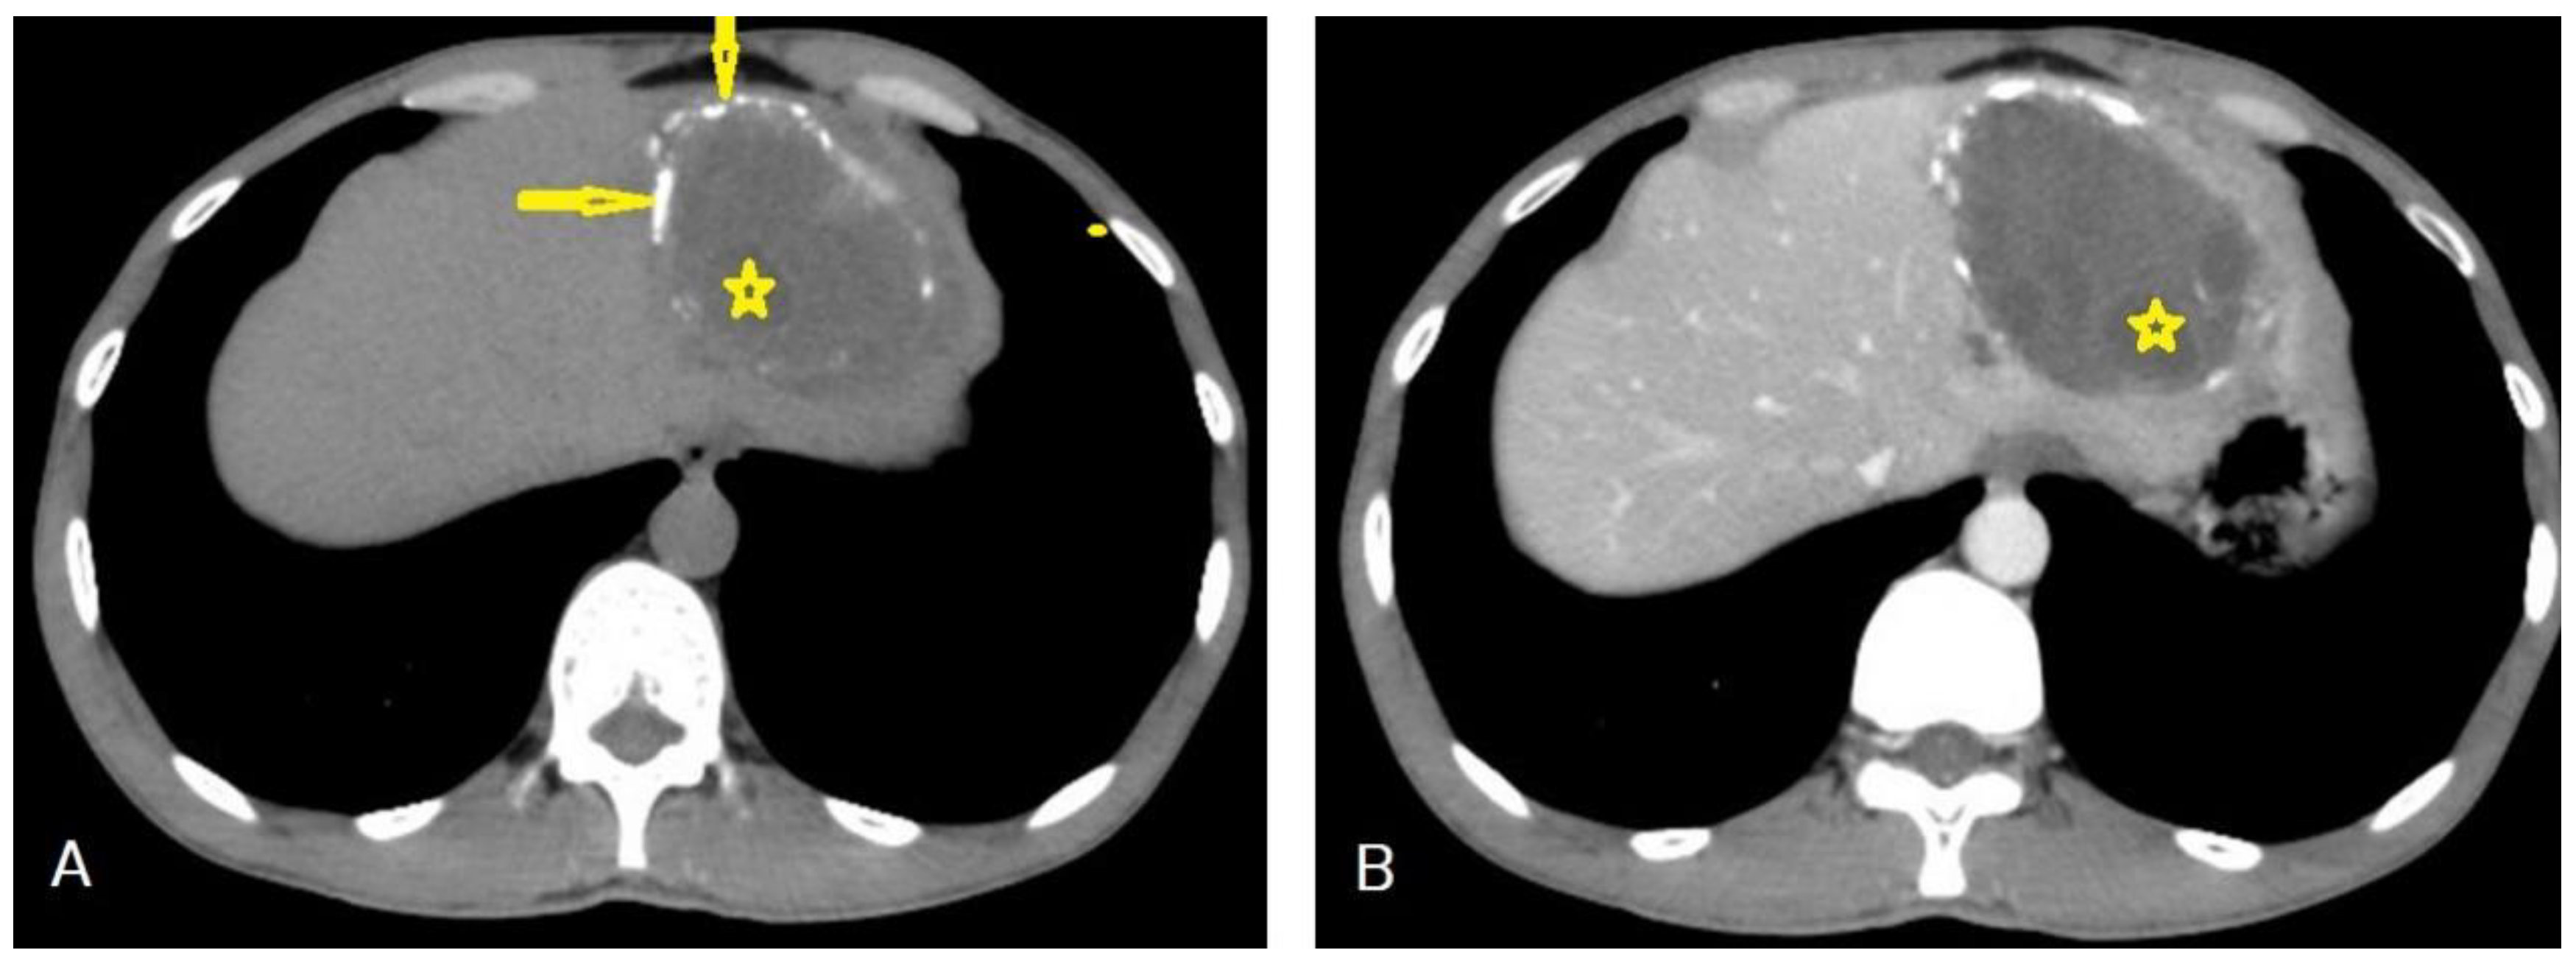

5.3. Hydatid Cysts of the Spleen